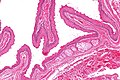

Steatocystoma. H&E stain. | |

| LM | cyst lined by squamous epithelium with a corrugated eosinophilic lining, no granular cell layer |

- Cyst lined by squamous epithelium with:

- Corrugated eosinophilic lining - key feature.

- Similar appearance to compact keratin (hyperkeratosis).

- Described as a hyaline cuticle.[5]

- No granular cell layer.